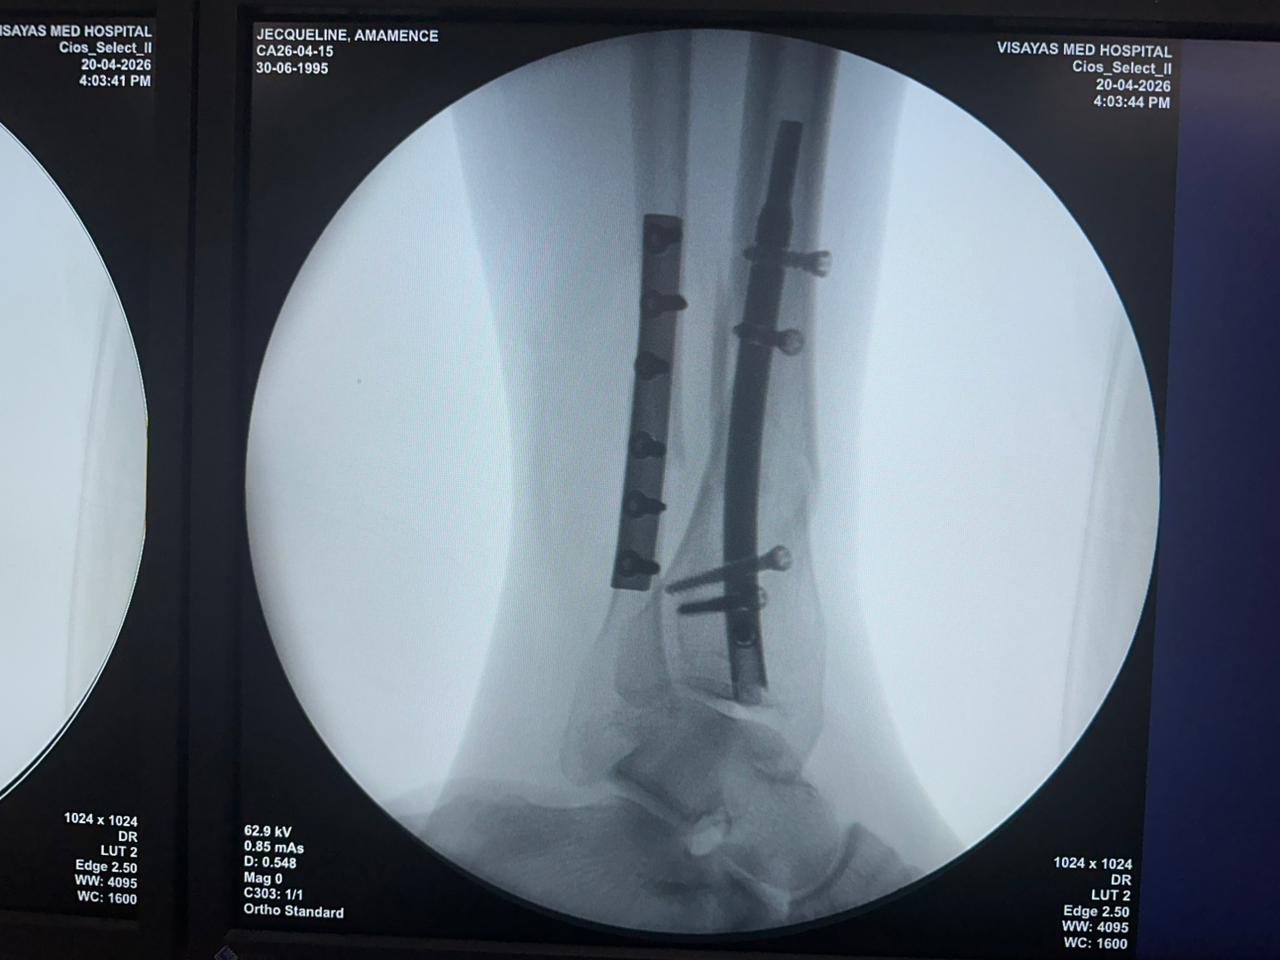

Distal Tibial Nail Fixation Case Study with Fibular Plate Support

Imaging:

Intraoperative C-arm fluoroscopy, AP and lateral views

Case Summary:

This case involved distal tibial fixation using an intramedullary distal tibial nail. Intraoperative fluoroscopy confirmed the position of the nail, distal locking screws, and fibular plate fixatio